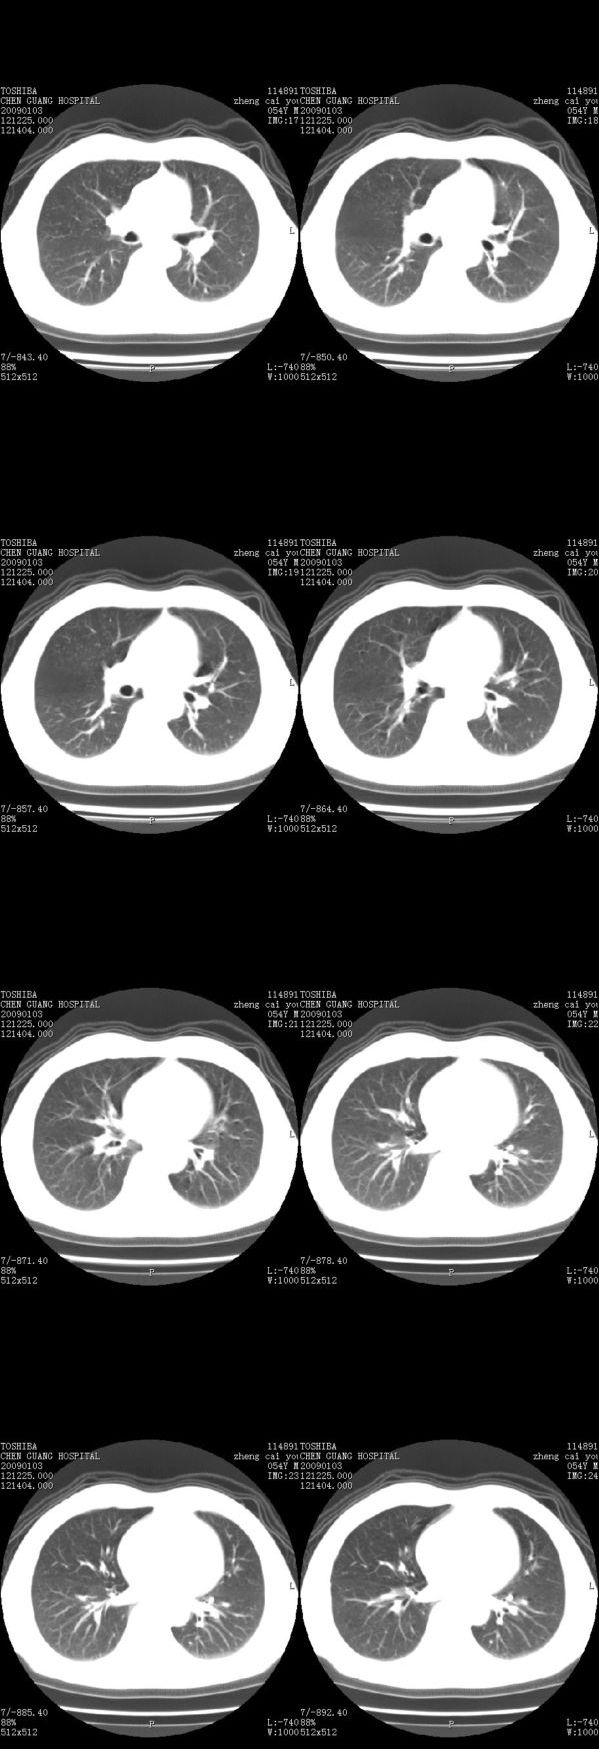

男,54岁,平时有吸烟后咳嗽、咯痰史,因右侧胸部(腋窝下)疼痛来检查平片,见右下肺动脉干起始处处结节,后到同学处做了平扫及增强。请各位老师帮忙看一下,不甚感谢!!!!!

支气管壁增厚

右肺下叶支气管扩张。

考虑------支气管壁增厚---局限性气肿---建议----气管镜进一步检查

考虑小气道堵塞,肺气肿。

小叶中心型肺气肿

肺窗薄扫、常规扫描均未见明确病变;右下肺门圆形与肺血管等密度影,考虑为血管变异;应该要纵隔窗才能进一步明辨。